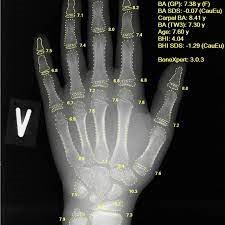

- Bone age X-rays: Typically of the left hand) which shows the Shape and size of bones change as a healthy person grows. Your doctor can see bone abnormalities with this x-ray. An expert compares your child's X-rays with the X-rays of other children the same age, and gives the bones an age in years. If a child's bone age is much younger than their actual age, this might be a sign of GH deficiency.